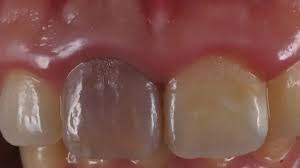

Lesión Traumática Pulpar

Una lesión traumática pulpar es un daño a la pulpa dental debido a un trauma, como un golpe en el diente.

Los pacientes pueden experimentar dolor, sensibilidad y decoloración del diente.

El tratamiento incluye evaluar la vitalidad de la pulpa y, si es necesario, realizar un tratamiento de conducto. Es importante tratar la lesión para evitar complicaciones a largo plazo.